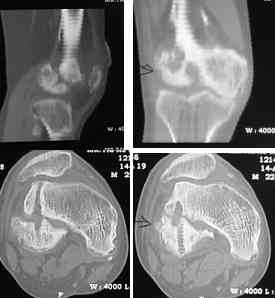

This 20 year old patient sustained a fracture in the lower end of the femur, one and a half years ago, with a compound wound over the fracture area. Notes at that time mention a compound fracture dislocation, with a loss of part of the lateral condyle. This was treated by debridement, and external fixation. After two weeks, the lateral condyle (coronal fracture) was fixed by a screw and k wire in an AP direction.

At present, he has a valgus deformity of the knee, with 0-45 degrees of movt. The knee is stable to examination, could not be corrected to neutral from the existing valgus, and despite the deformity he is walking on it, albeit with pain and some difficulty.

I cannot make certain from the AP whether the screw and KW are still present. The lateral however shows that the lateral condyle was fixed with disregard to the bone defect. So it was proximally displaced in relation to the medial condyle with the resultant valgus. I would do an open wedge osteotomy with bone graft and internal fixation. However, this would require a precise estimate of the correction angle and placement of the fixation device. I would use a DCS.